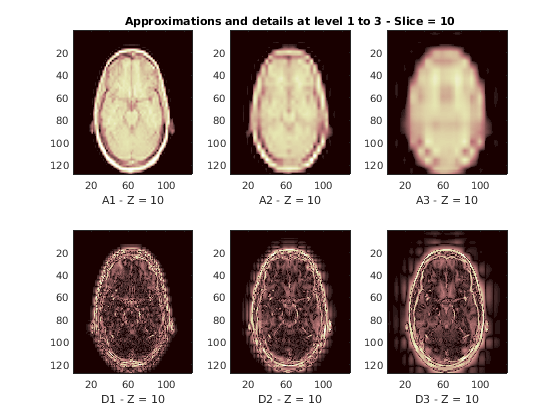

Восстановленные приближения и детали вдоль Z-ориентации отображены ниже.

nbIMG = 6; idxImages_New = [1 7 10 16 19 25]; for ik = 1:nbIMG j = idxImages_New(ik); figure('DefaultAxesXTick',[],'DefaultAxesYTick',[],... 'DefaultAxesFontSize',8,'Color','w') colormap(map) for k = 1:n labstr = [int2str(k) ' - Z = ' int2str(j)]; subplot(2,n,k); image(A{k}(:,:,j)); xlabel(['A' labstr]); if k==2 title(['Approximations and details at level 1 to 3 - Slice = ' num2str(j)]); end subplot(2,n,k+n); imagesc(abs(D{k}(:,:,j))); xlabel(['D' labstr]); end end